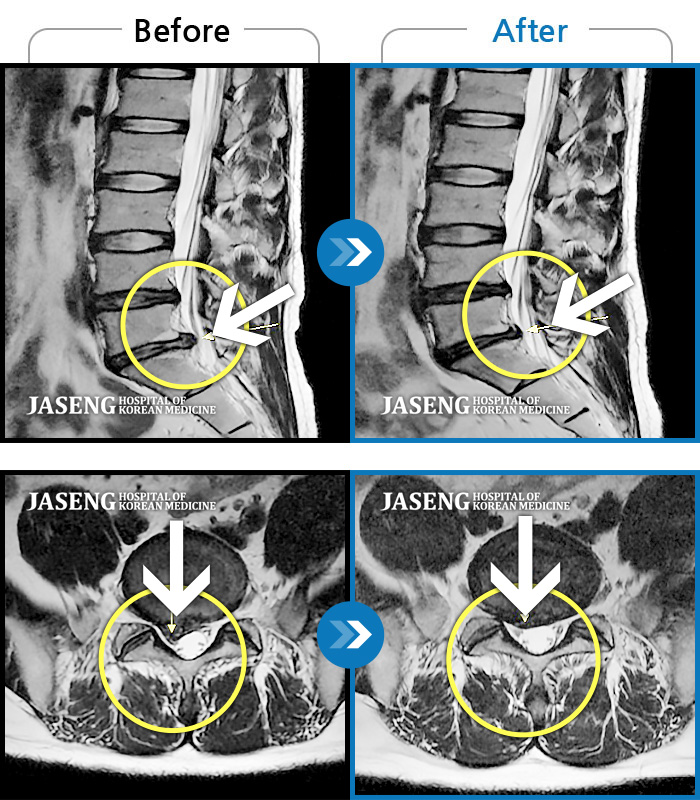

허리디스크

울산 · 정운석 원장

양측 하요추부 통증과 우측 하지 저림

촬영시기

2022.03.16 ~ 2022.11.12

2023.01.19